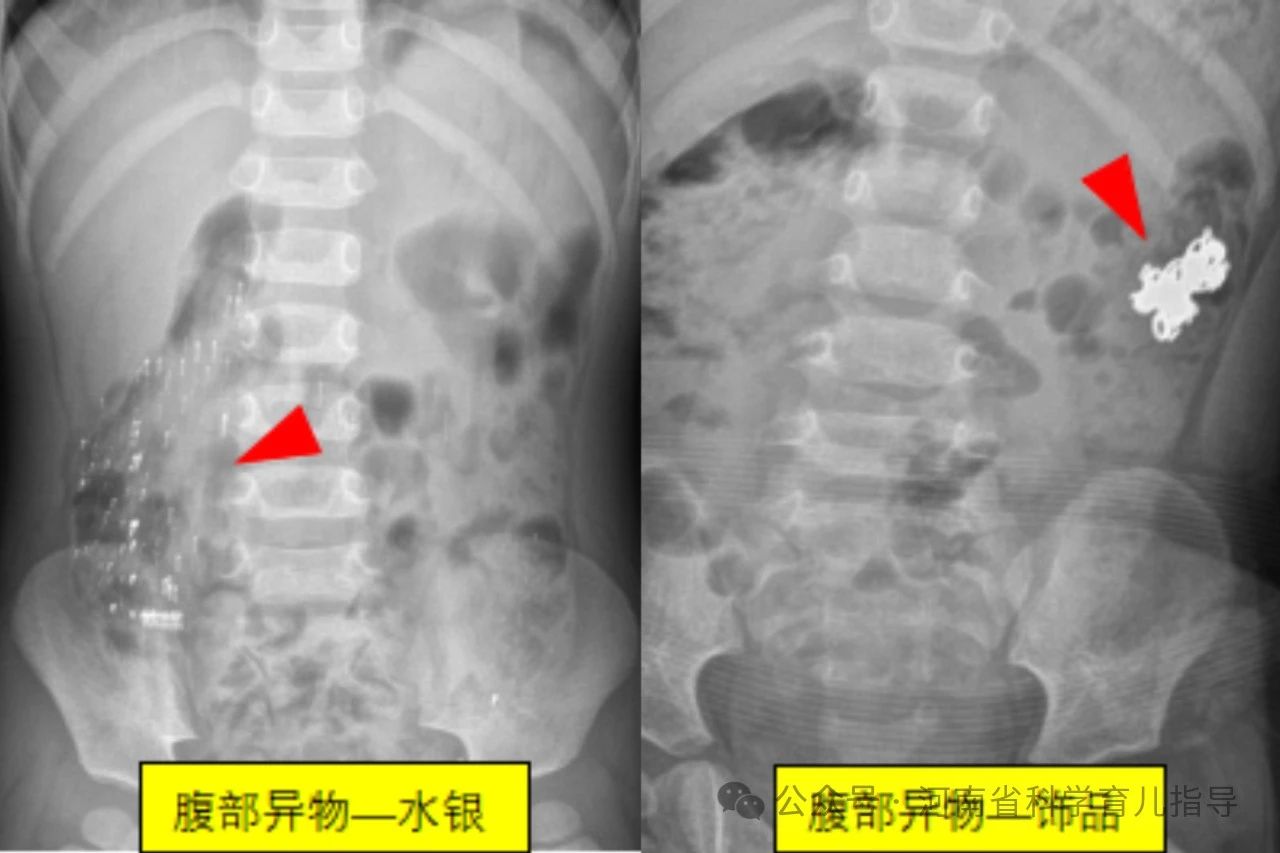

消化道异物儿童消化道异物是指儿童误吞了不能被消化且未及时排出而滞留在消化道的各种物体,文献中已报道的有硬币、果核、碎骨、电池、磁性异物、玩具、指甲、乳牙、笔头、塑料笔帽、电动牙刷头、大头针、戒指、图钉、螺丝钉、别针、纽扣、毛发等等。根据其形状主要包括以下几种,圆钝型异物如硬币,钢珠,螺丝帽,电池,棋子等圆形或者边缘比较平钝、光滑的物体,扁平状或球型。尖锐型异物如针状,钉状或者钩状物体,还有不规则型异物如女性的金属饰品发卡,生活用品如温度计中的水银等。其中形状不规则或者尖锐异物、纽扣电池、多枚磁性异物或单枚磁性异物合并金属异物发生并发症的风险较高,危险性较大。

经搜集我们郑州大学第三附属医院医学影像科最近7年间的图像存储系统的X线报告,查找可疑小儿消化道异物的病例541例,即家长发现家中某些东西不见了,但未直接看见或不确定孩子是否吞咽异物。通过X线拍片检查确认存在消化道异物病例共338例,阳性病例约62.5%。338例消化道异物中硬币183例,磁力珠15例,电池20例,水银22例,磁铁3例,钢针7例,钢珠10例,钉类14例,围棋子7例,其他个别如发卡,手链,钥匙,戒指,果核,易拉罐环,子弹头,纽扣,拉链等少数。发生消化道异物的小儿年龄最小的3个月,最大的6岁。23例在1岁以内,且多数在6个月到1岁之间;1岁74例,2岁94例,3岁77例,4岁43例,5岁24例,6岁3例。由此可以看出小儿发生消化道异物的年龄大多数在1~5岁之间,当然1岁以下甚至3个月的小婴儿也可以发生,这需要家长朋友们特别注意。

圆钝型异物形态规则,边缘比较光滑,短时间不会对身体造成伤害。较大的异物可能会卡在消化道生理性狭窄的部位,如口咽部,食道或胃窦幽门部等引起不适或者机械性梗阻,需要请专业医生借助专用器械取出。较小的异物一般情况下容易通过消化道自然排泄出来,家长朋友们无需过多担心和焦虑,根据孩子的大便习惯,观察确认异物排出即可。但纽扣电池存在腐蚀性化学成分,会对存留部位造成腐蚀伤,不同时间吞咽多个磁力珠会因其磁力相互吸引对肠道进行挤压造成肠道缺血坏死,最好能及时发现,尽早取出,减少伤害。